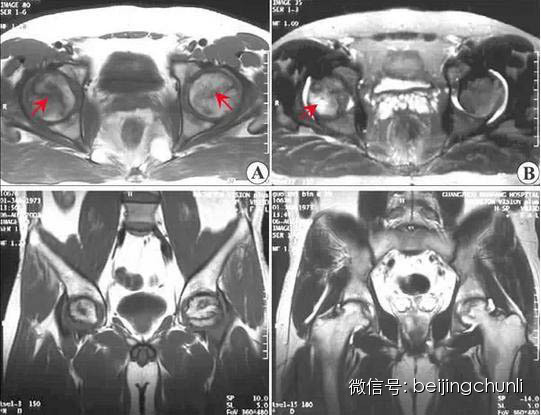

3股骨头坏死的 MRI 表现

MRI 敏感性优于骨核素扫描和 CT 及 X 线检查。这是因为股骨头发生坏死后,修复组织不断伸入坏死区上方骨髓的变化早于骨质变化,MRI可以在骨质塌陷及修复以前反映出骨髓细胞的变化。所以,MRI应作为早期检查诊断骨坏死的主要手段。

0期 一般患者无症状,病理表现为造血骨髓的丢失,胞浆滞留并有窦状小管,间质内积液和骨髓脂肪细胞的坏死。MRI可表现正常,在骨扫描时局部呈现一示踪剂缺血性冷点。只在 MRI 动态扫描时上述冷点可表现为增强减弱。

I期 股骨头不变形,关节间隙正常,X 线平片、CT多不能显示明显的骨质病变,称X线前期。T1加权股骨头负重区(根据关节软骨结构和功能的特点,将股骨头软骨面分为三个部份,外上方与髋臼软骨面相差的压力负重区、压力负重区内侧的非压力负重区和外侧周围的非压力负重区)显示线样低信号。T2加权呈高信号病理特征,是骨和骨髓的坏死无修复,以骨髓水肿、骨细胞坏死、骨陷窝空虚为主要改变。

Ⅱ期 股骨头不变形,关节间隙正常。T1加权为新月形边界清楚的不均匀信号,T2加权显中等稍高信号,周围不均匀稍低信号环绕,呈典型的双线征,位置基本与CT的条状骨硬化一致。病理上为病灶中心大量不规则的细胞碎片坏死,周边纤维化,新骨形成和肉芽组织增生。

股骨头坏死

上图为II期

Ⅲ期股骨头变形,软骨下骨折、塌陷、新月体形成。T1加权呈带状低信号,T2加权示中等或高信号,为关节积液进入软骨下骨折线的裂隙。新月形坏死骨发生应力性软骨下骨折、塌陷并与关节软骨分离。由于纤维组织长入形成致密的无血管墙,使修复被阻挡,进入坏死骨的修复受限。

上图为Ⅲ期